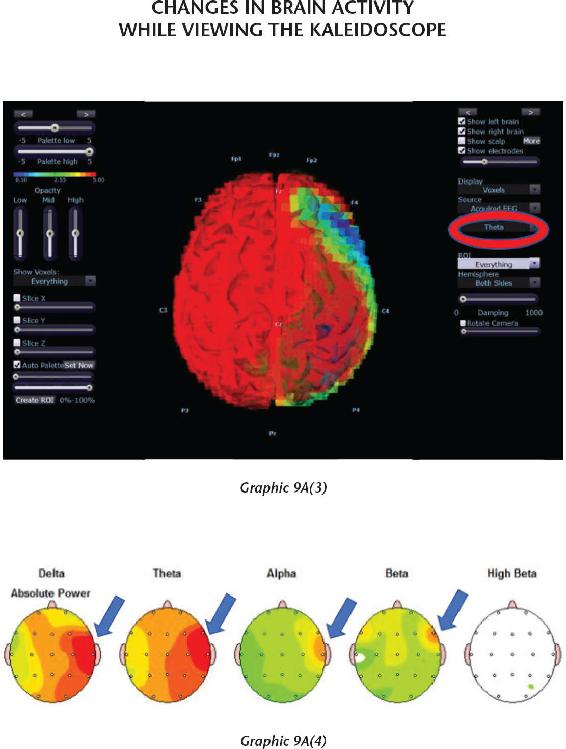

We have thousands and thousands of brain scans that prove those changes were not just imagined in their minds but actually took place in their brains. Several of the students we measured accomplished those changes within four days (the length of our advanced workshops). The scientific teams I’ve assembled have taken brain scan recordings using quantitative electroencephalogram (EEG) measurements before and after workshops as well as real-time measurements during the meditations and practices themselves. I was not only impressed with the changes, but shocked by them—they were that dramatic.

The brains of our students function in a more synchronized and coherent fashion after participating in the advanced retreats around the world. This increased order in their nervous systems helps them get very clear about a future they can create, and they are able to hold that intention independent of the conditions in their external environment. And when their brains are working right, they are working right. I will present scientific data that shows how much their brains improved in just a few days—which means you can do the same for your brain.

Chapter 8 shares one of the other favorite activities we do at our advanced workshops: combining a kaleidoscope with videos called Mind Movies that our students make of their future. We use the kaleidoscope to induce a trance because when you are in trance you are more suggestible to information. Suggestibility is your ability to accept, believe, and surrender to information without any analysis. If you do this properly, it is indeed possible to program your subconscious mind. So it makes sense that when you use the kaleidoscope to change your brain waves—with your eyes open instead of closed in a meditation—you can lower the volume of the analytical mind to open the door between the conscious mind and the subconscious mind.